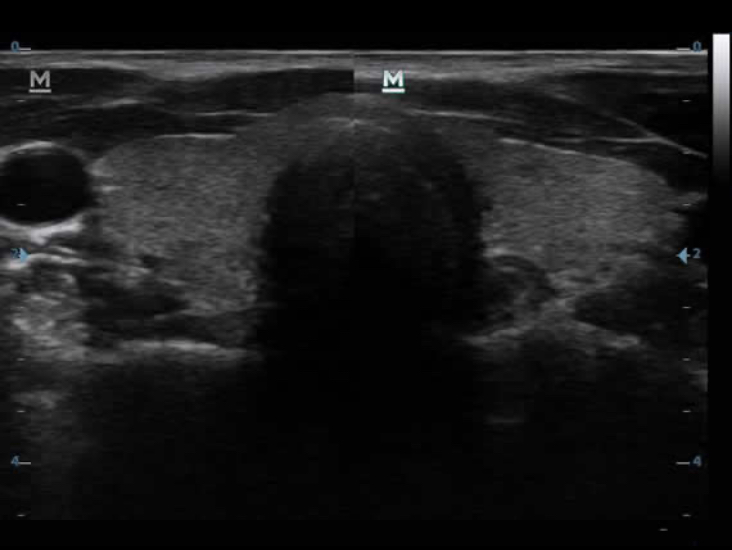

ImĂĄgenes por armĂłnicos tisulares (THI)

Mediante el uso de los segundos armĂłnicos generados a partir de las capas lĂmite de tejido, el sistema de THI mejora significativamente la resoluciĂłn de contraste y la calidad de la imagen, especialmente en sujetos tĂ©cnicamente difĂciles.?